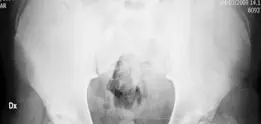

الأشعة السينية الأمامية الخلفية للحوض (AP Pelvis Radiograph):

تظهر هذه الأشعة صورة شاملة للحوض ومفصلي الورك. في حالة المريض، أظهرت الأشعة تسطحًا غير منتظم واندفاعًا للمشاش (epiphysis extrusion)، وعدم وجود عنق فخذ واضح، وارتفاع المدور الكبير، وقصر في الساق بمقدار 2 سم.

الصورة 1.7: أشعة سينية أمامية خلفية للحوض تظهر تسطحًا غير منتظم واندفاعًا للمشاش، عدم وجود عنق فخذ، ارتفاع المدور الكبير، وقصر في الساق بمقدار 2 سم.